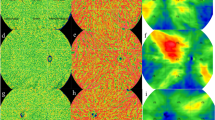

The structures in the OCT volume including sclera appear curved due to the spherical shape of the eye. Consequently, to get enface slices of the sclera it is required to restructure the OCT volumes to make the sclera flat. In other words, the scleral region below choroid-sclera interface (CSI) should be flattened. To this end, COB detection is a crucial step in localizing sclera below the choroid. We adopted a modified version of our previous reported method23 to segment COB. The previous method had two main limitations: (i) detection of CIB and COB was based on two separate approaches and the structural similarity (SSIM) technique employed earlier for obtaining initial COB estimate was computationally intensive; and (ii) individual B-scan processing was performed and inter-slice dependency within the B-scans of a OCT volume was not considered while detecting CIB and COB which may not result in seamless (spatially consistent) boundaries across B-scans. In view of this, in the modified methodology we made two new contributions to address the aforementioned limitations. In particular, they include (i) obtaining initial estimates of both CIB and COB based on single technique i.e., using a two-step exponentiation enhancement method inspired by idiosyncrasies of the OCT imaging; and (ii) performing volumetric smoothing, to correct spurious detection in initial estimates of CIB and COB, leveraging the inherent neighborhood dependency among the B-scans of an OCT volume. The schematic of the proposed method for detecting CIB and COB is depicted in Fig. 3, and corresponding implementation output of each step are shown in Fig. 4 based on a representative OCT B-scan (Fig. 4b) of an OCT volume (Fig. 4a). The coordinate orientation of the XYZ axis of OCT volume is also depicted in Fig. 3a. In particular, the proposed method involves (i) detecting initial CIB estimate sequentially in each B-scan and stack all estimates in 3D; (ii) obtaining final estimate of CIB by smoothing in orthogonal direction to the B-scan orientation; (iii) detecting initial COB estimate sequentially in each B-scan and stack all estimates in 3D; and (iv) obtaining final COB estimate by adopting step (ii) of CIB to COB. Step-by-step details of the method are described in the following.

Graphical representation of the proposed algorithm; (a) a typical optical coherence tomography (OCT) volume scan; (b) a representative B-scan from the OCT volume to illustrate operations performed on a B-scan; (c) second order median filtered image; (d) adaptive histogram equalization; (e) vertically flipped image; (f) binarization based on two step exponentiation enhancement; (g) morphologically processed image; (h) detected CIB; (i) initial CIB estimate (green); (j) final CIB estimate (yellow); (k) binarization based on exponential and non-linear enhancement processes; (l) vessel section extracted image based on nal COB and morphological operations; (m) identification of extreme point in each column belonging to vessel sections towards sclera; (n) interpolation based on 2D tensor voting; (o) initial COB estimate (green) vs manual segmentations M1 and M2 (red and magenta); (p) final COB estimate (yellow) vs M1 and M2; and (q) Segmented boundaries on the whole volume (CIB choroidal inner boundary, COB choroidal outer boundary).